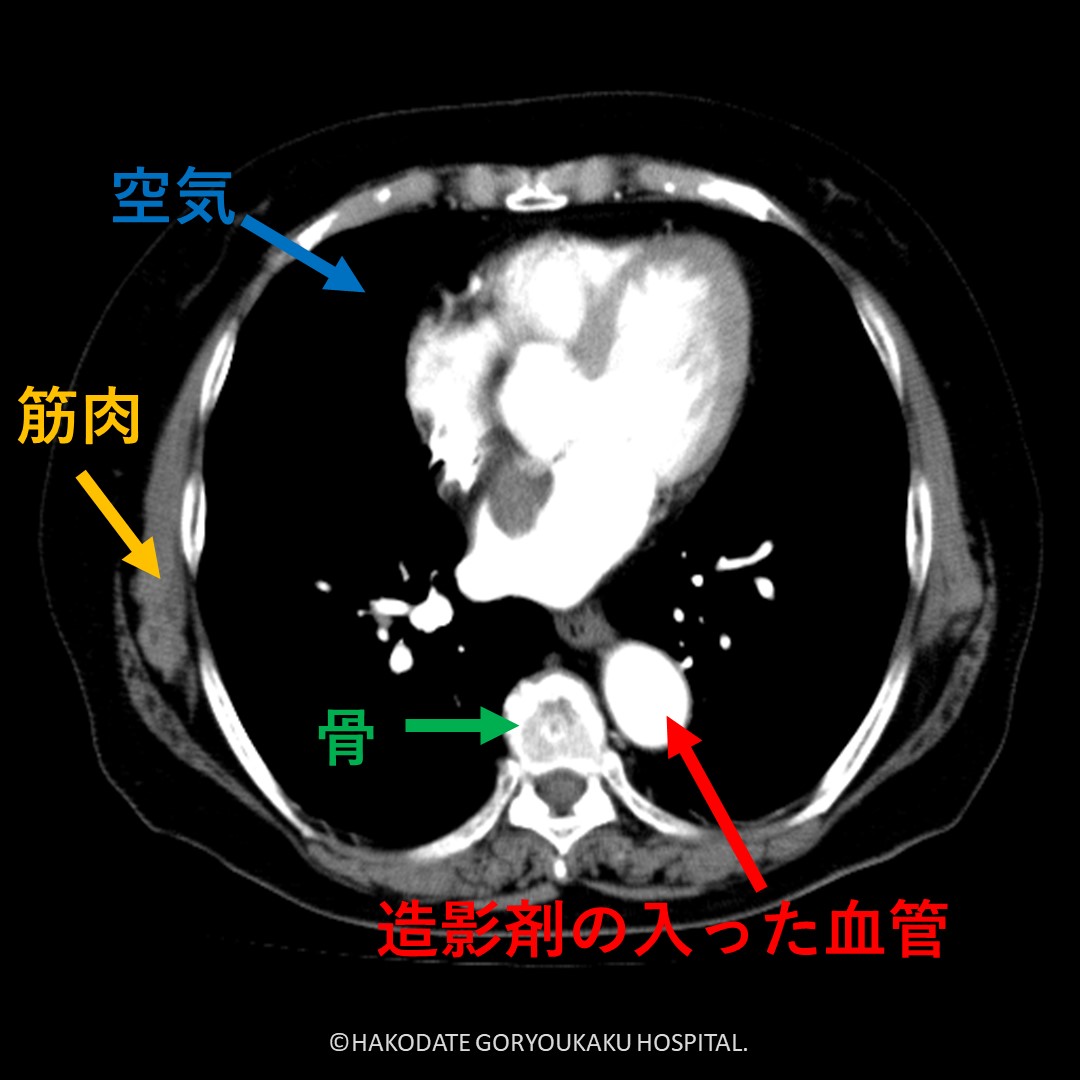

CT画像は「体の中の輪切り写真」

白く見えるところ・黒く見えるところ

CT画像では、写るものによって色の濃さが異なります。

□ 白く見えるもの:骨、造影剤が入った血管、金属など

□ 黒く見えるもの:空気(肺や腸の中など)

□ 灰色に見えるもの:筋肉や臓器(肝臓、腎臓など)

白く写っているからといって、必ずしも異常があるわけではありません。体の中には、もともと白く写るもの・黒く写るものがたくさんありますので、見た目だけで判断する必要はありません。